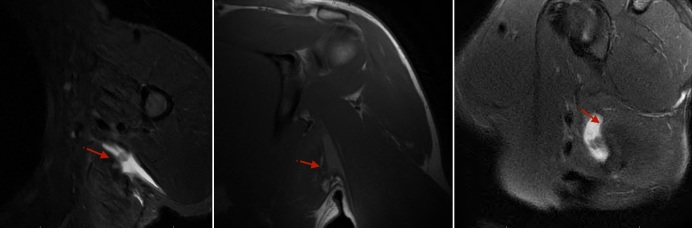

本病例报告和技术说明详细介绍了采用单切口腋窝入路和全缝合锚定张力滑动技术成功修复高需求运动员背阔肌肌腱断裂的手术。患者是一名38岁的竞技运动员,在斯巴达比赛中受伤,表现出严重的功能限制,包括肩部无力和运动和专业活动中的表现受损。临床和影像学结果证实了完全性LD肌腱断裂,并伴有6厘米的内陷和相关的大圆肌部分撕裂。手术修复包括肌腱活动,肱骨足迹的准备,以及在张力滑动结构中用全缝线锚钉固定。术后,患者接受了量身定制的康复方案,在7个月后几乎完全恢复到损伤前的功能。这种创新的技术有很多优点,包括美容切口、手术并发症最小化以及熟悉运动外科医生的技术。与皮质钮扣相比,全缝线锚钉避免了金属植入,减少了骨质流失,简化了手术过程。虽然有效,但该方法需要技术专长,特别是在减轻神经血管风险方面。本报告强调了该方法治疗高需求运动员LD肌腱断裂的有效性和可重复性。进一步的生物力学和临床比较是必要的,以完善手术适应证和优化结果。

This case report and technical note details the successful surgical repair of a latissimus dorsi (LD) tendon rupture in a high-demand athlete using a single-incision axillary approach with an all-suture anchor tension slide technique. The patient, a 38-year-old competitive athlete, sustained the injury during a Spartan Race, presenting with substantial functional limitations, including shoulder weakness and impaired performance in athletic and professional activities. Clinical and imaging findings confirmed a complete LD tendon rupture with 6 cm of retraction and associated teres major partial tearing. Surgical repair involved tendon mobilization, preparation of the humeral footprint, and fixation with all-suture anchors in a tension slide configuration. Postoperatively, the patient underwent a tailored rehabilitation protocol, achieving near-complete return to preinjury function by 7 months. This innovative technique offered advantages, including cosmetic incision, minimized surgical morbidity, and familiarity with sports surgeons' techniques. The all-suture anchors avoid metal implants, reduce bone loss, and simplify the procedure compared to cortical buttons. Although effective, the approach requires technical expertise, particularly in mitigating neurovascular risks. This report underscores the efficacy and reproducibility of this method in treating LD tendon ruptures in high-demand athletes. Further biomechanical and clinical comparisons are warranted to refine surgical indications and optimize outcomes.